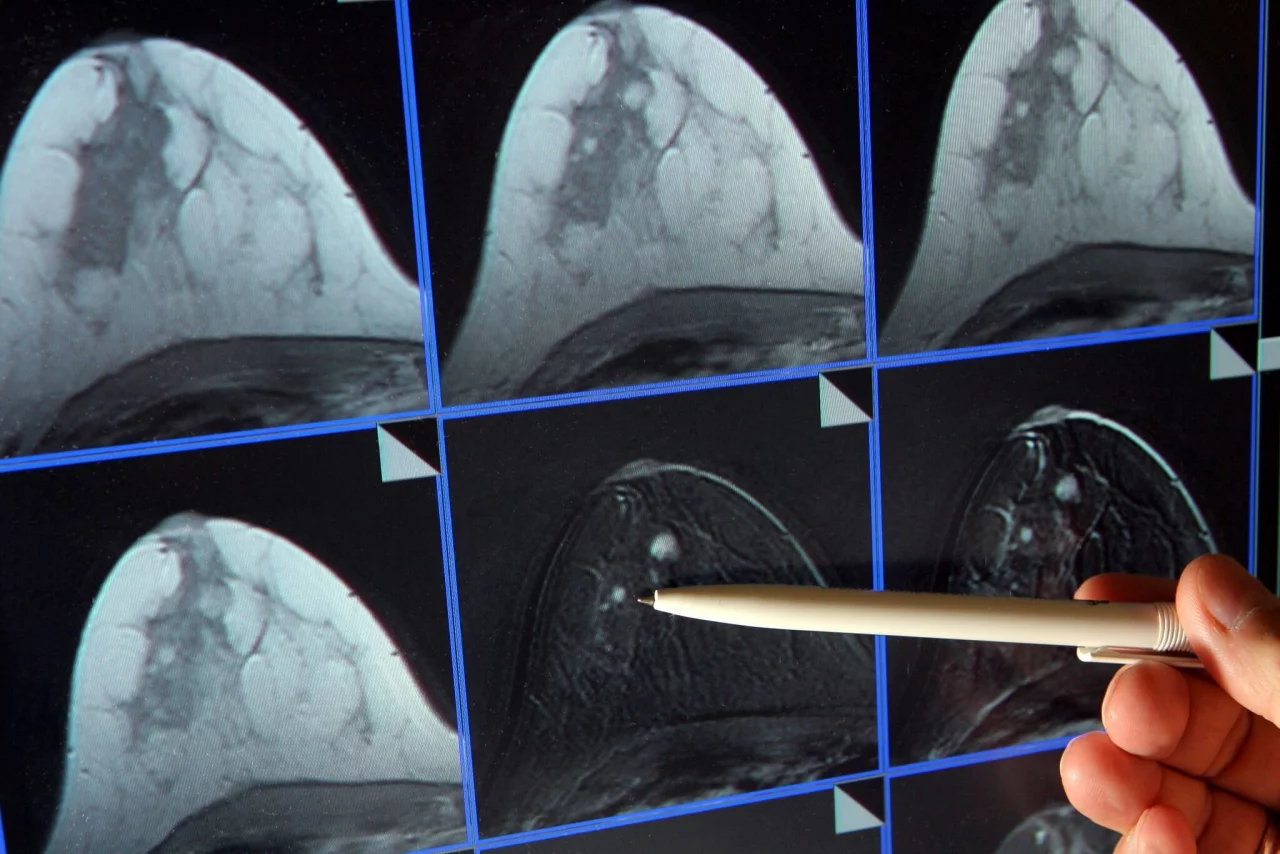

Kuhl ist überzeugt, dass sich die Zahl der an Brustkrebs sterbenden Frauen stark senken ließe. Dazu müsse die Früherkennung besser individuell angepasst werden. So sollten etwa Frauen mit sehr dichtem Brustgewebe, bei denen eine Mammografie nicht ausreicht, alternative Früherkennungsverfahren angeboten werden – insbesondere die Magnetresonanztomographie (MRT), für die es die höchste wissenschaftliche Evidenz gebe. Dieses Verfahren liefere umso bessere Nachweise, je aggressiver ein Karzinom sei.

MRT - bei vielen Frauen die weitaus bessere Wahl?

Etwa zehn Prozent der Frauen haben ein extrem dichtes Brustgewebe. Sie würden durch das derzeitige Mammografie-Screening unterversorgt, heißt es auch von der Europäischen Gesellschaft für Brustbildgebung (EUSOBI). Es gebe Nachweise, dass MRT-Untersuchungen die Brustkrebs-Sterblichkeit bei ihnen erheblich senken könne. Frauen sollten von ihren Ärzten generell über ihre Brustdichte informiert werden. Die Fachgesellschaft empfiehlt, Frauen im Alter von 50 bis 70 Jahren mit extrem dichter Brust alle zwei bis vier Jahre ein MRT-Screening anzubieten.

In Deutschland müssen Frauen in diesen Fällen MRT-Untersuchungen selbst zahlen. Die gesetzlichen Krankenkassen übernehmen die etwa 350 Euro für eine Früherkennungs-MRT nur bei einem nachweislich deutlich erhöhten Risiko für Brustkrebs – etwa bei einer BRCA1- oder BRCA2-Genmutation oder familiärer Belastung. «Auch wenn Mammografie und Ultraschall keine eindeutigen Ergebnisse liefern, kann ein MRT zur weiteren Abklärung von unklaren Befunden eingesetzt werden», erklärte Kolberg.